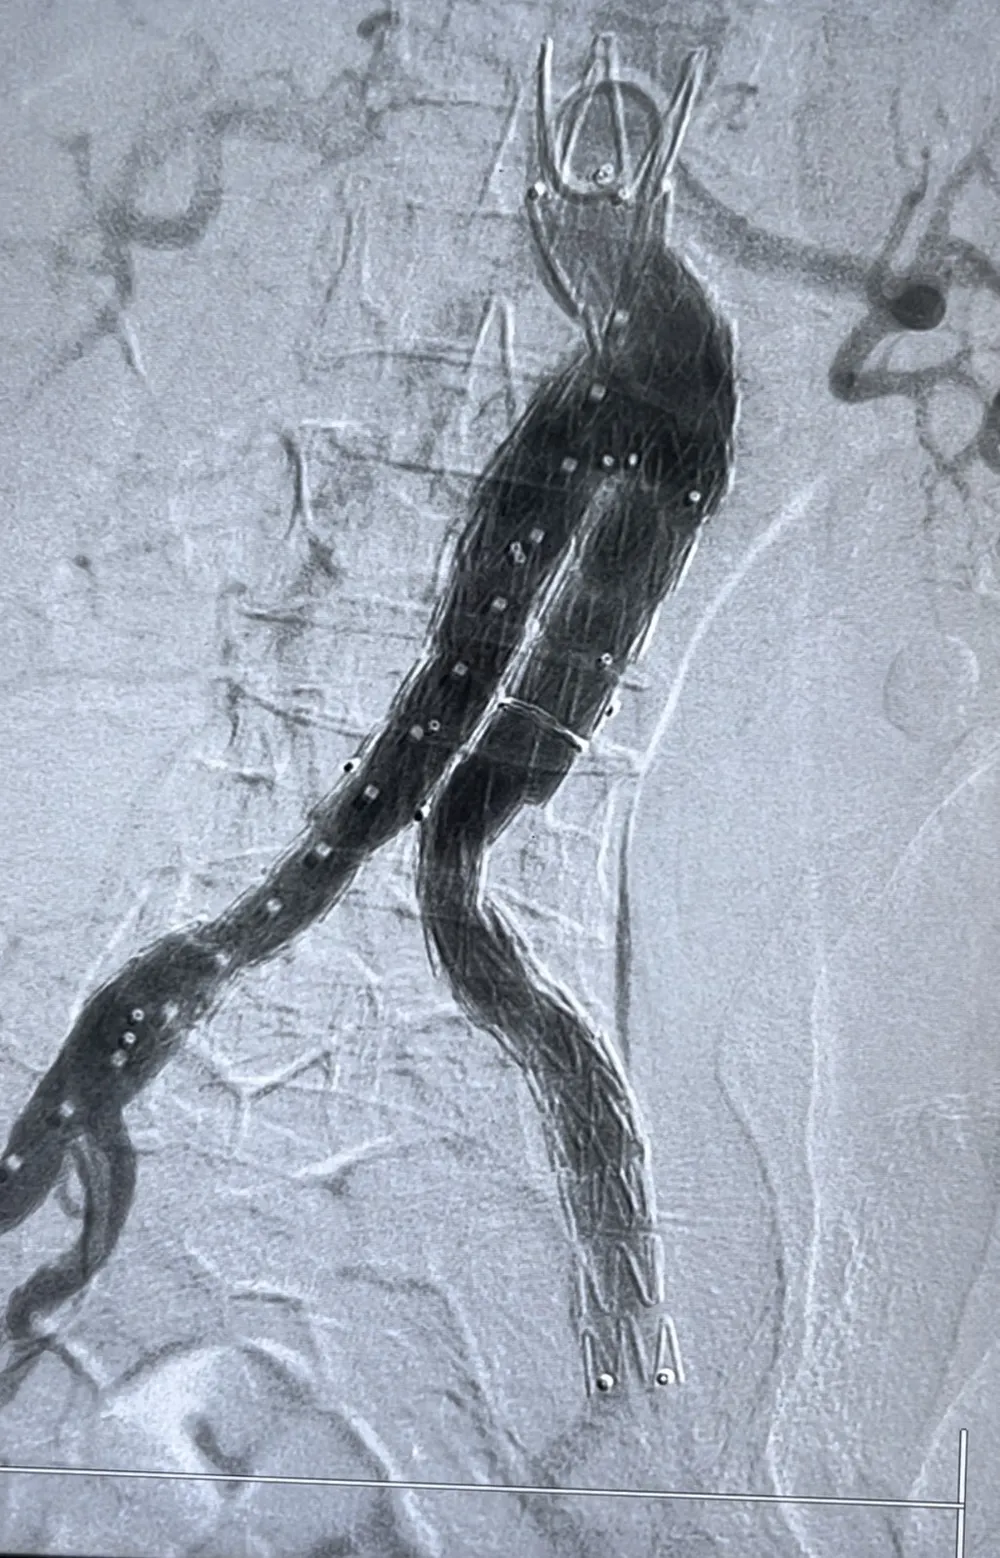

![]() |

Động mạch chủ của bệnh nhân trước khi can thiệp |